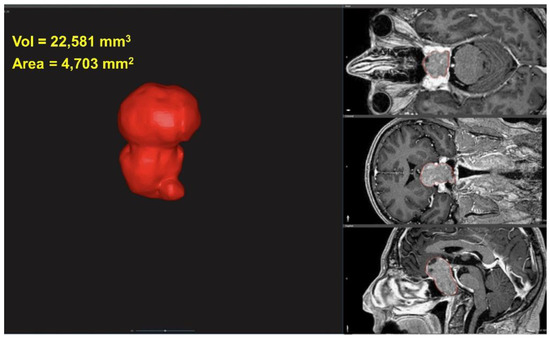

2.2. 3D Characterization of Tumor

2.3. Tumor Volume and Area

2.4. Tumor Sphericity

2.5. Tumor Convexity